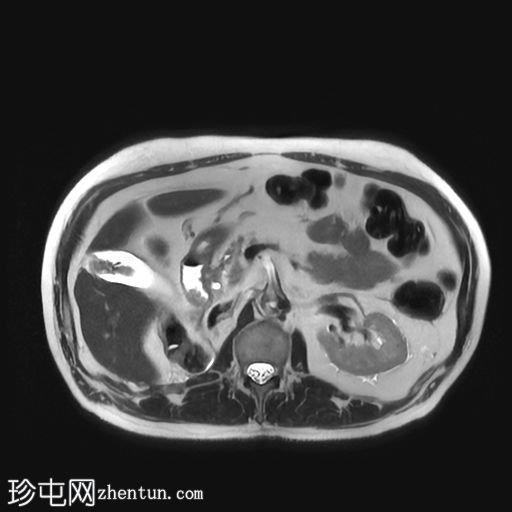

轴位T1加权像

4.jpg

同相位

5.jpg

反相位

增强扫描(C+)脂肪抑制

行MRI检查以明确病因。 MRI显示胆囊底部有一孤立性息肉样病变,突入胆囊内,大小约为21 mm x 17 mm。病变表面可见高T1信号,可能代表血液成分。病变早期增强扫描后强化程度较正常胆囊壁更为明显。